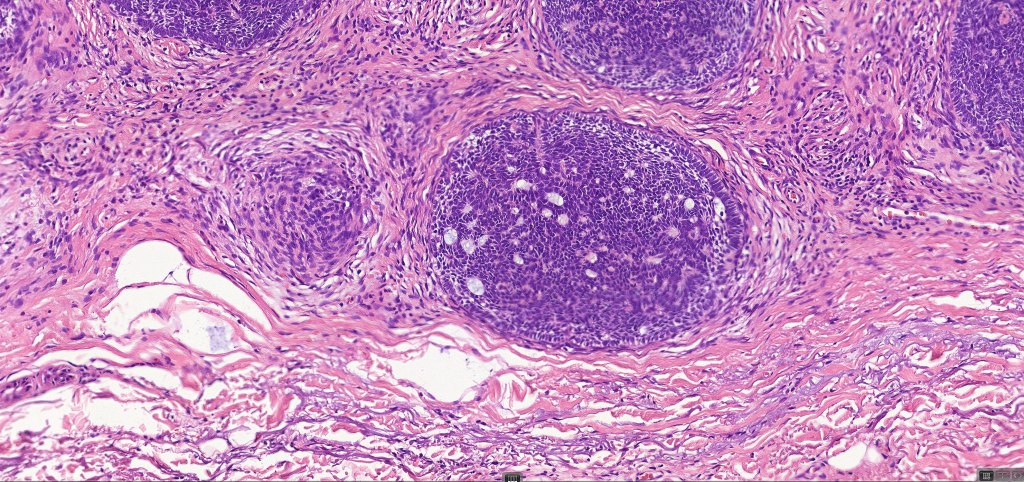

•Variable keratocysts

•A rich fibromyxoid mesenchymal stroma with variable papillary mesenchymal bodies (sometimes these are absent)

•Trichogerminoma is a distinctive variant being composed of tumor nodules with basaloid cells surrounding pale or eosinophilic micronodules (Zellballen)